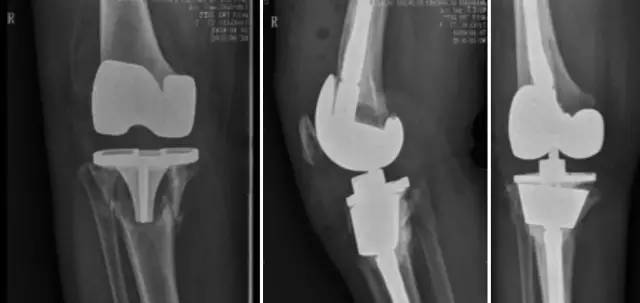

各种晚期骨关节病的关节置换手术治疗是北京清华长庚医院关节外科中心的一大特色,包括股骨头坏死、髋膝骨关节炎、类风湿关节炎、强直性脊柱炎、髋关节发育不良、关节强直、超过80岁的超高龄股骨颈骨折患者的关节置换手术等,我中心在人工关节初次置换及翻修上作了大量工作,置换的难度和手术效果方面已达到国际先进水平,导航下全膝关节置换术:大大提高膝关节置换手术的精确度。

局限性关节置换手术(UKA)

全膝关节表面置换手术(TKA)

铰链式人工膝关节置换手术(HK)膝关节周围韧带严重破坏

国内首例膝关节置换术后Felix IIB型胫骨假体周围骨折翻修术